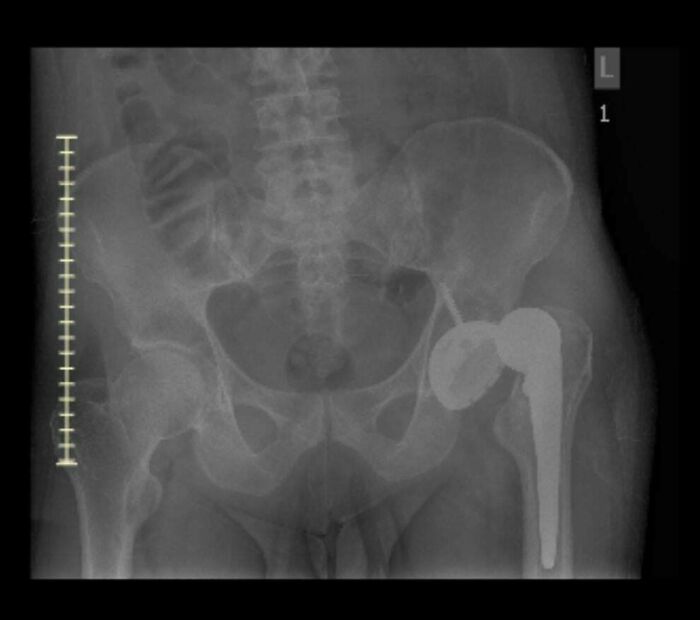

#30 My Hip Died From Avn, Then I Woke Up In The Hospital Recovery Room Not Knowing The Replacement Was Dislocated

Some general info on my situation. Had developed on and off pain in my left leg/hip for years till it got so bad I couldn’t put my full weight on it, which is when I got in for the first image showing an MRI slice of the dead hip. Eventually I was able to get the hip arthroplasty done. I awoke in recovery with my leg flat on the bed. I complained to the initial Nurse’s & PT people that it felt weird & shorter than it should be. The Drs and surgeon said normally patients felt it was longer, but it felt shorter to me and those initial people after the surgery told me that what I felt was “normal”… I figured I just had a hip replacement & it’d be painful… ~1.5 months later they did a Xray & well, that’s why I couldn’t walk like I’d read I should have been able too. Anteriorly dislocated the whole time. I kept bringing it up about it feeling weird with the med related people I was seeing… I suppose I was a bit stoic & didn’t give the right number of the pain that I felt. Just thought they knew better than me. I feel like I have a permanent muscle knot at this point.

Image source: SomeDumbPenguin